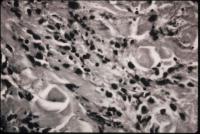

Typical microscopic findings of fibrosis and perivascular leukocytic infiltration.